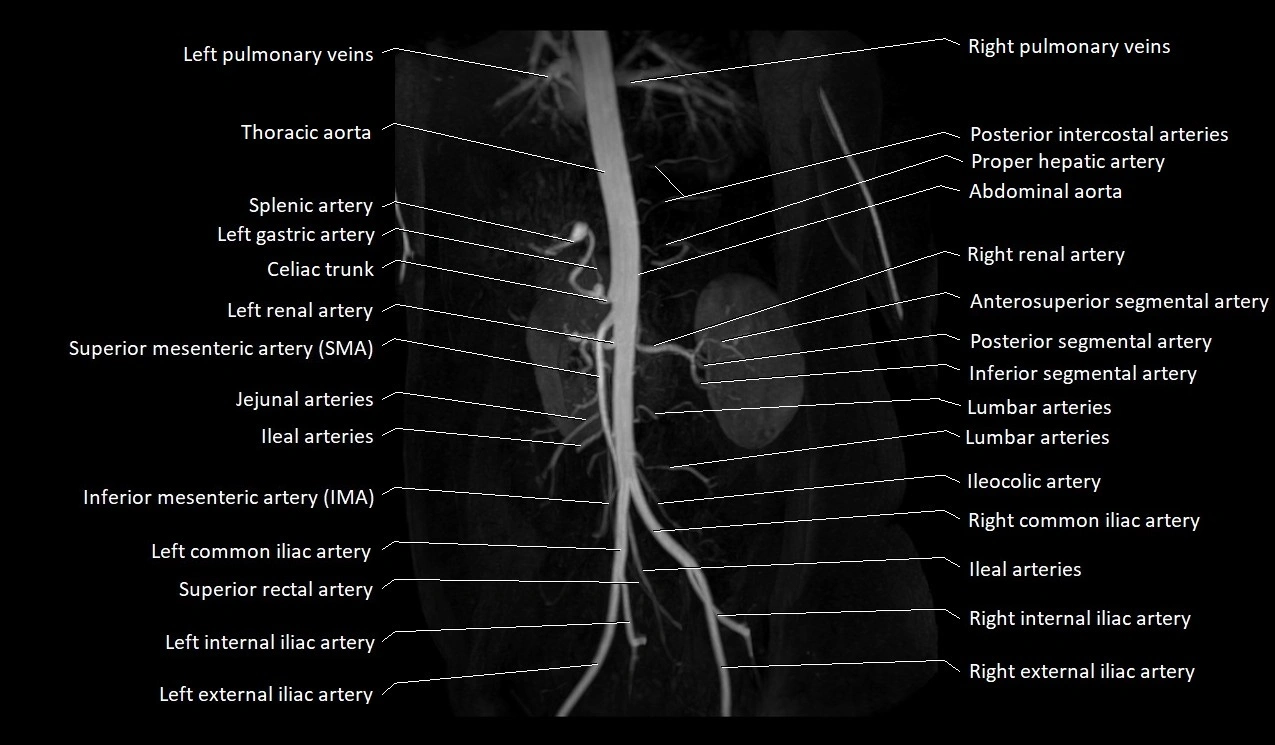

MRA (Magnetic Resonance Angiography):

• Contrast-enhanced MRA provides high-resolution imaging of the aorta and its branches

• Allows 3D reconstruction of visceral, parietal, and terminal branches

• Excellent for evaluating aneurysm size, dissection flap, stenosis, or preoperative planning

• Non-invasive alternative to conventional angiography

CT images

image